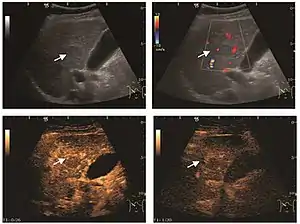

It is a tumor developed secondary to a circulatory abnormality with abundant arterial vessels having a characteristic location in the center of the tumor, within a fibrotic scar. A radial vessels network develops from this level with peripheral orientation. The tumor's circulatory bed is rich in microcirculatory and portal venous elements. The incidence is higher in younger women and tumor development is accelerated by oral contraceptives intake. 2D ultrasound appearance is a fairly well-defined mass, with variable sizes, usually single, solid consistency with inhomogeneous structure. Rarely the central scar can be distinguished. Spectral Doppler examination detects central arterial vessels and CFM exploration reveals their radial position. CEUS examination shows central tumor filling of the circulatory bed during arterial phase and completely enhancement during portal venous phase. During this phase the center of the lesion becomes hypoechoic, enhancing the tumor scar. During the late phase the tumor remains isoechoic to the liver, which strengthens the diagnosis of benign lesion.

HCC appearance on 2D ultrasound is that of a solid tumor, with imprecise delineation, with heterogeneous structure, uni- or multilocular (encephaloid form). An "infiltrative" type is also described which is difficult to discriminate from liver nodular reconstruction in cirrhosis. Typically HCC invades liver vessels, primarily the portal veins but also the hepatic veins . Doppler examination detects a high speed arterial flow and low impedance index (correlated with described changes in tumor angiogenesis). The spatial distribution of the vessels is irregular, disordered. CEUS examination shows hyperenhancement of the lesion during the arterial phase. During the portal venous phase there is a specific "wash out" of ultrasound contrast agent (UCA) and the tumor appears hypoechoic during the late phase. Poorly differentiated tumors may have a stronger wash out leading to an isoechoic appearance to the liver parenchyma during portal venous phase. This appearance was found in approx. 30% of cases. The described changes have diagnostic value in liver nodules larger than 2 cm.